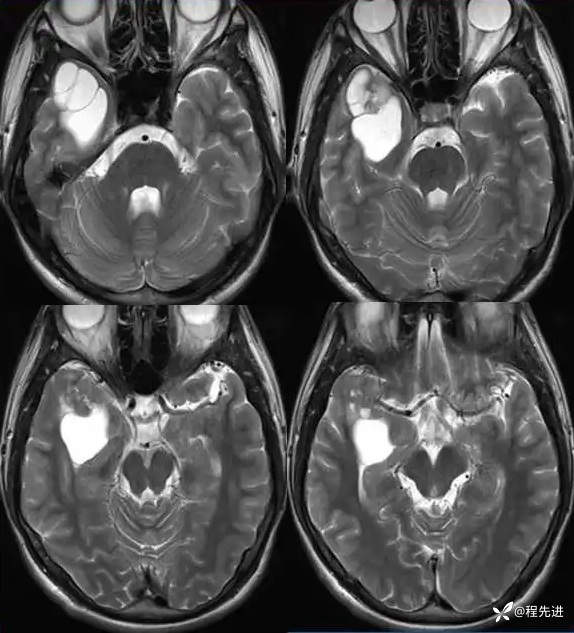

T2: